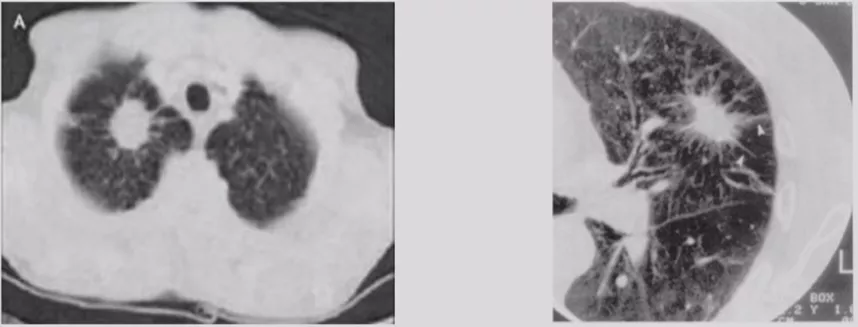

局灶性机化性肺炎

机化性肺炎有一个特点,它会有动态变化,大小和形态都有很大的变异,形态不规则呈多角形,贴近胸膜面(可有局限性胸腔积液)或沿支气管血管束分布,有粗长毛刺、尖角、向心性弓形凹陷、支气管扩张,部分病灶中心可出现低密度区(增强时呈周围强化),部分病灶边缘可见肺泡隔增厚而使边缘清晰,纵膈、肺门淋巴结增大较少见。

浸润性腺癌(IA)

病灶较前几种类型更大,多为实性或以实性成分为主(>5mm,GGO比例<50%)的结节,形状多为不规则,边界较清楚,开始出现一些明显的肿瘤征象,可有分叶、毛刺、棘突、空泡征、支气管充气征、血管集束征、胸膜牵拉征等。临床医生判断这些征象没有什么问题,但是这个时候对于呼吸医生来说,应该在这之前给病人一个比较合理的判断。